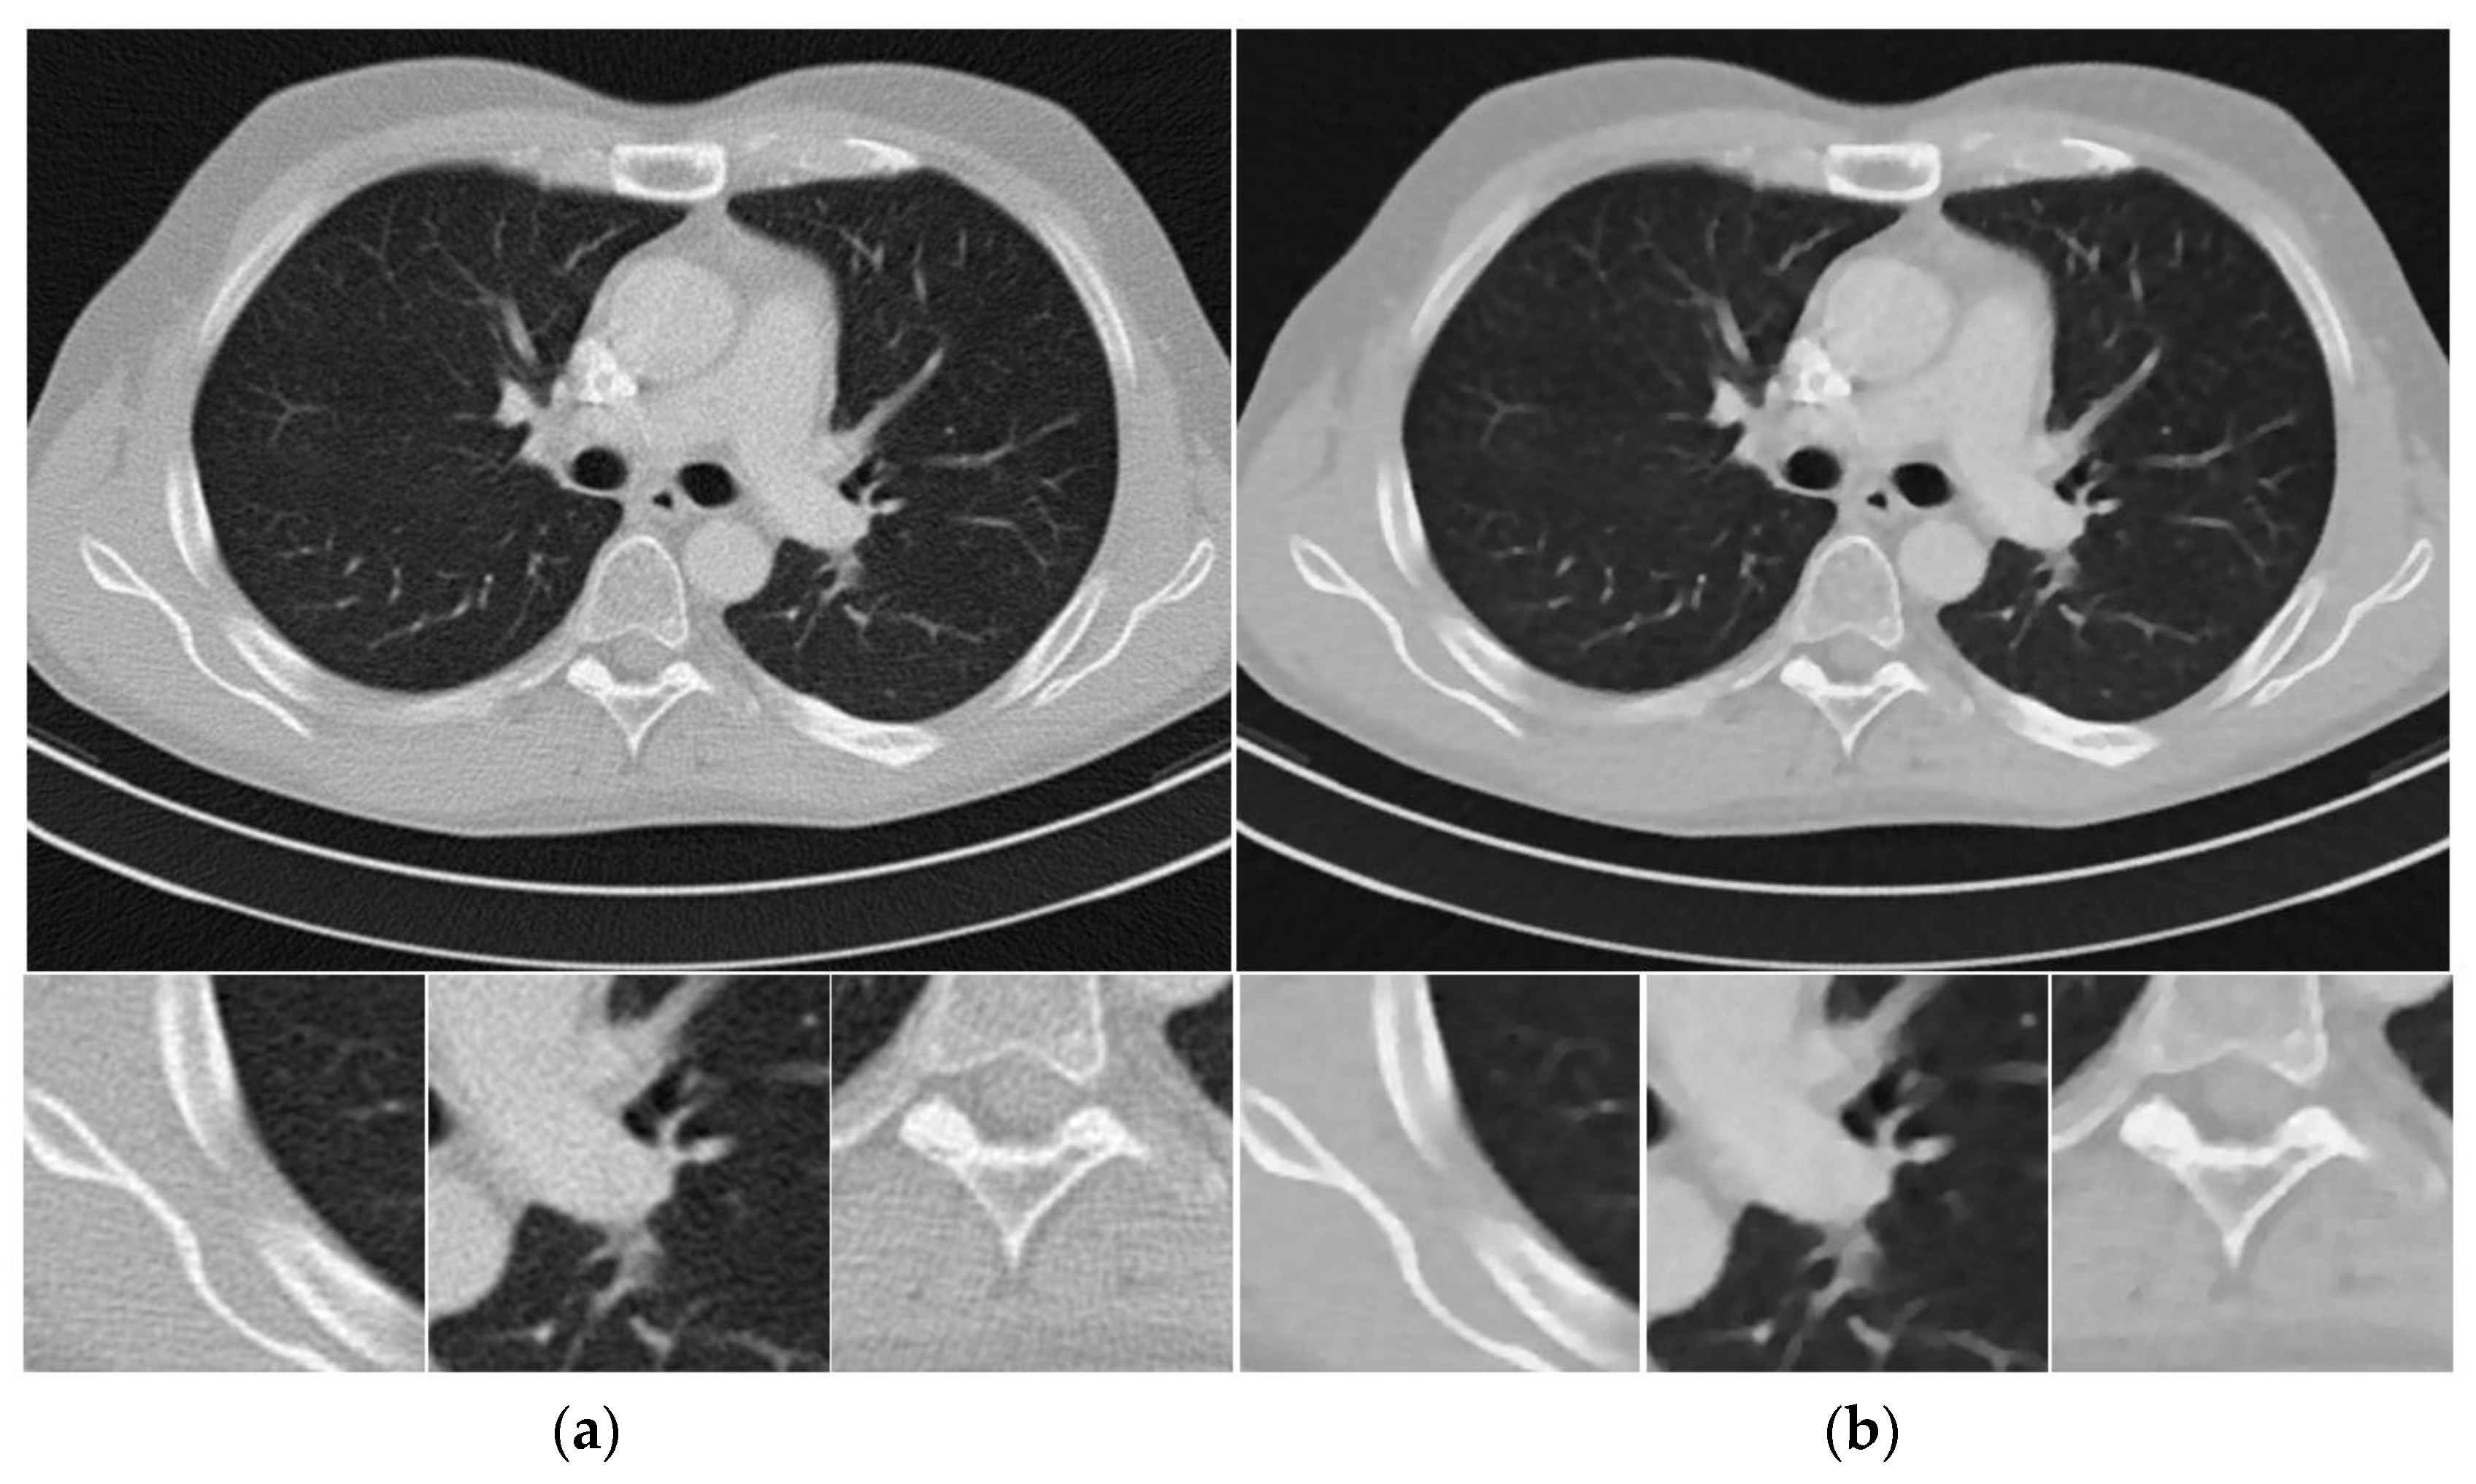

3.2.1. Visual Quality Comparison

Figure 4 shows the reconstructed images from noisy projections with incident photon numbers 5 × 104 by the FBP, SIR-TV, and SIR- STV1 methods. In the proposed SIR-STV1 method, σ is set to 0.5, L K is set to be 3, and λ is set to 2 × 10 6 . It can be seen that SIR-TV and SIR-STV1 can remove noise effectively and the SIR-STV1 method performs better in eliminating blocky effect than SIR-TV.

Figure 4. Thorax CT images reconstructed by (a) FBP, (b) SIR-TV, and (c) SIR-STV1 methods from noisy projections with 5 × 104 incident photon number. The display window is [−1000, 667] HU.